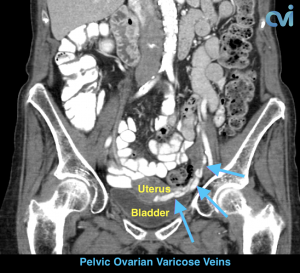

Pelvic Congestion Syndrome (PCS) or Pelvic Venous Congestion Syndrome (PVCS) is essentially varicose veins of the ovaries. Varicose veins are most commonly seen in the legs and are caused by the veins becoming less elastic resulting in abnormal flow of blood causing it to pool in certain areas, leading to enlarged painful veins. This is also what happens to the pelvic veins in pelvic congestion syndrome.

The abnormal veins dilate and cause varicose veins around the ovary and uterus because the valves don’t work properly. Blood flow is in the wrong direction, pooling in the veins and causing them to enlarge.

PCS can be diagnosed by Ultrasound or CT of the Abdomen and Pelvis.

Magnetic resonance imaging (MRI) and computed tomography (CT) is another method to diagnose pelvic congestion syndrome. Our practice requires a CT of the Abdomen and Pelvis with contrast prior to treatment. This allows us to see where the varicose veins are coming from so that we can plan and do the appropriate treatment. Sometimes there are abnormal pelvic veins in addition to the ovarian veins that need treatment. Sometimes PCS can be missed on CT if the contrast injection is not timed appropriately or the vein is not directly measured.